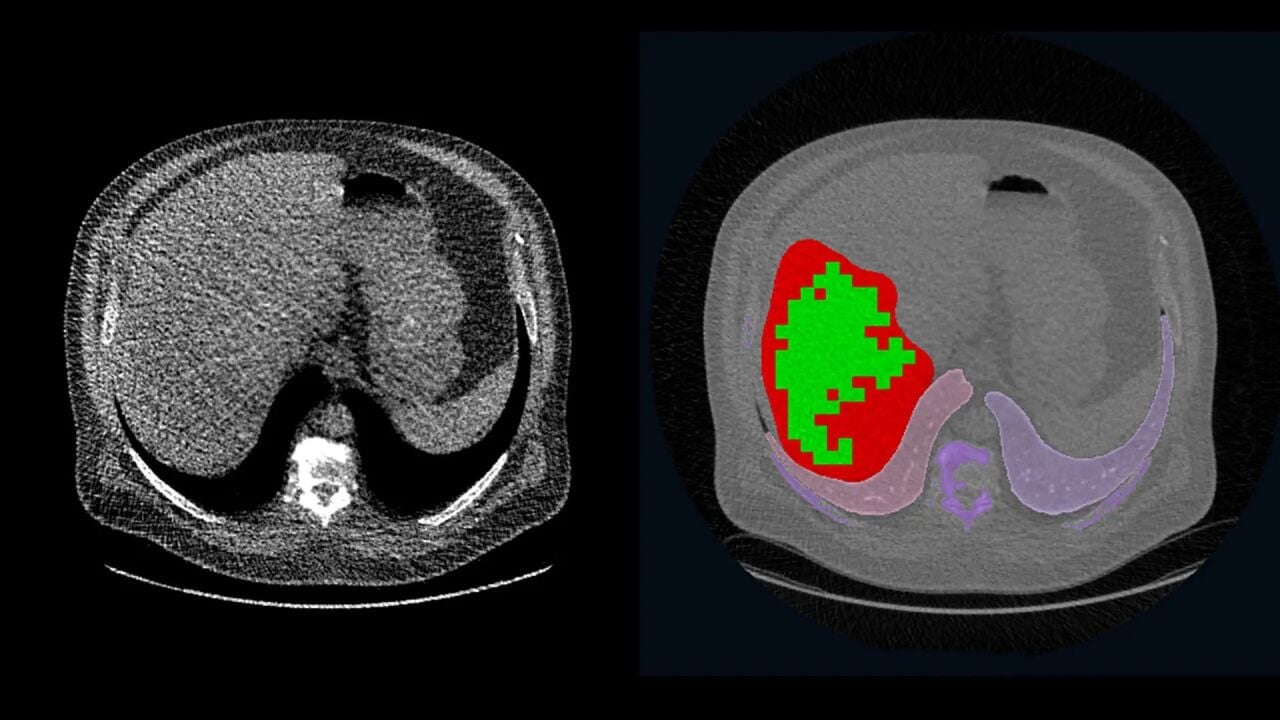

Karaciğer Görüntüleme Testleri (Ultrason, MR, BT) ve Sonuçların Yorumlanması

Karaciğer yağlanması, leke, siroz ya da tümör mü? Karaciğer ultrasonu, MR ve BT ile erken teşhis mümkün! Ağrısız testlerle detaylı inceleme yaptır, sağlığını riske atmadan önlemini al. Karaciğerini ihmal etme, vaktinde kontrol ettir!